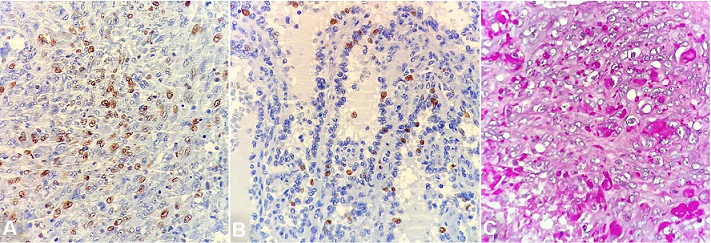

The spleen was enlarged, weighing 1200g (RR: 112g) and measuring 18.0 × 13.0 × 6.5 cm. The splenic capsule had multiple disrupted areas with fibrin deposition. Macroscopic sections showed multiple ill-defined nodular areas; the larger ones were white and firm and smaller ones were blue-red and spongy ( Figure 2). On microscopy, the spleen parenchyma was replaced by anastomosing, irregularly ectatic vascular channels lined by plump mildly atypical lining cells. Intercalated solid fusiform areas consisted of spindle cell fascicles showing moderate nuclear atypia, with frequent mitotic figures. These closely packed vascular channels were filled with red blood cells. Small eosinophilic globules identified in the cytoplasm of the spindle cells were highlighted by periodic-acid Schiff (PAS) reagent ( Figures 3 and 4).

Immunohistochemistry demonstrated diffuse positivity for CD31 and FLI-1 in both the spongy and the solid fusiform areas. However, CD34 was reactive only in the fusiform areas. D2-40 was not demonstrated. There was no positive expression for CD8, CD68, lysozyme or CD21 on the tumor cells. The Ki-67 index was increased (about 50%) in the spindle cell areas when compared to the spongy areas (about 10%) ( Figures 5 and 6). Despite the morphological aspects of littoral cell hemangioma, the presence of atypia, the high index of the Ki67 and the immunophenotype were consistent with angiosarcoma.